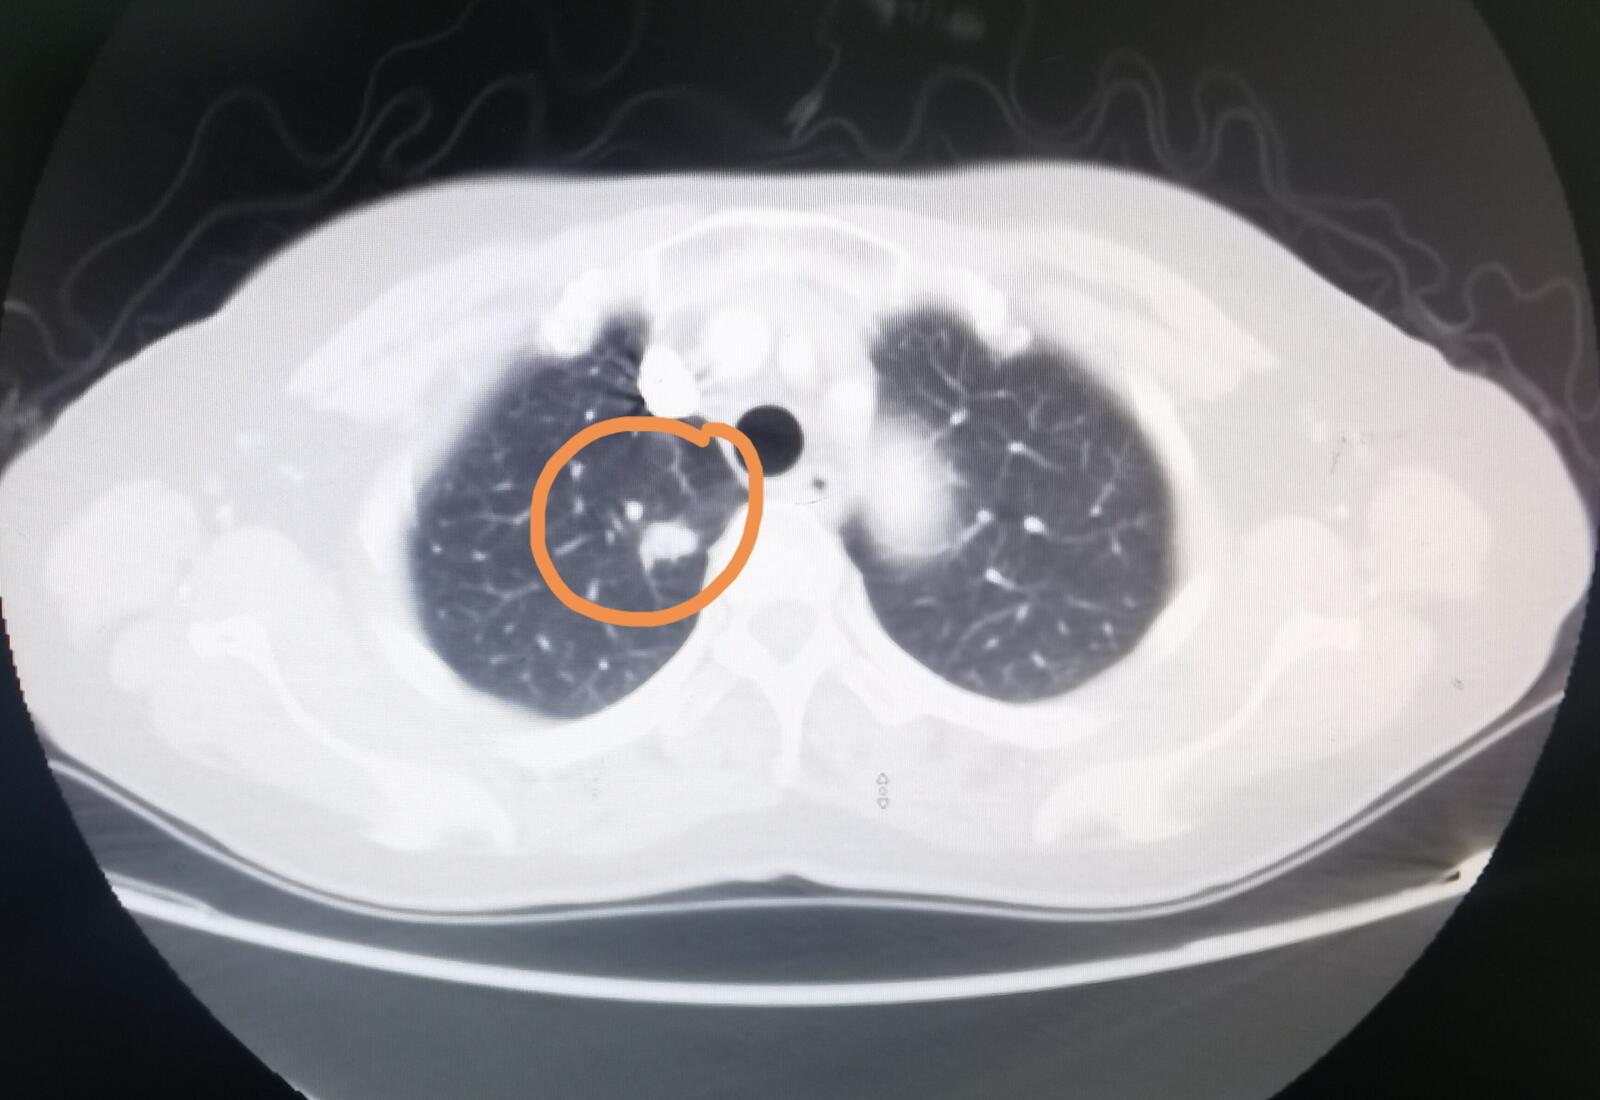

这位女士的肺结节位于右肺上叶,是一个实性肺结节,直径在一厘米出头,虽然有些层面的边缘是比较光滑的,但看起来还是像一个早期肺癌,该做手术了,我建议住进来争取手术。这位女士在我这里办理了住院,进行了手术,术后的病理显示是一个浸润性的肺腺癌。